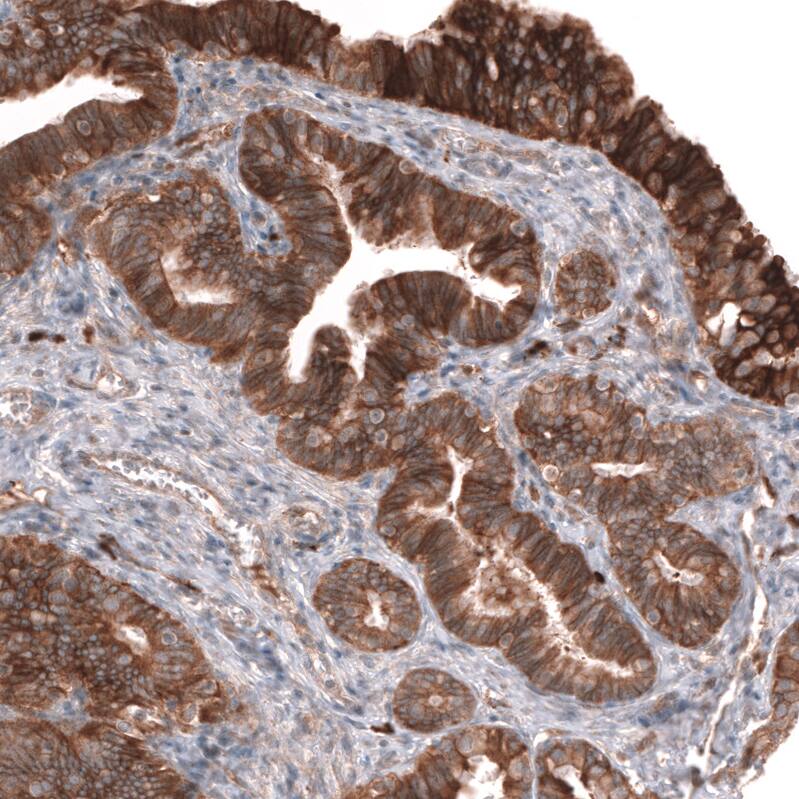

ADAM10 Antibody (CL13808) - Azide and BSA Free Immunohistochemistry-Paraffin: ADAM10 Antibody [NBP3-43825]

Immunohistochemistry-Paraffin: ADAM10 Antibody [NBP3-43825]

Staining of human kidney shows weak to moderate membranous positivity in cells in tubules.